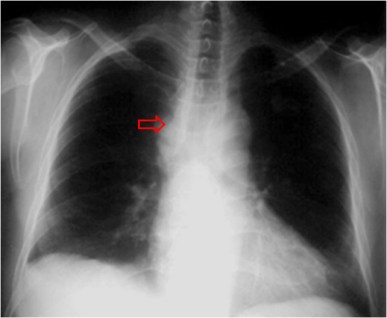

SIGNO DEL ESPACIO LIBRE

En la radiografía postero-anterior de tórax, en condiciones normales, existe un espacio libre delimitado por el arco aórtico, la arteria pulmonar izquierda y los vasos de lóbulo superior izquierdo. Este espacio también es conocido como ventana aorto-pulmonar). La ocupación de este espacio de lugar a la formación de un margen externo convexo en la ventana aorto-pulmonar, que puede ser el primer signo de la presencia de una adenopatía mediastínica izquierda y una señal de neoplasia o enfermedad granulomatosa.

Mostramos un paciente con adenopatías en la ventana aorto-pulmonar (flecha), que también presenta adenopatías hiliares.

Radiografía PA normal con la ventana aorto-pulmonar normal (flecha).